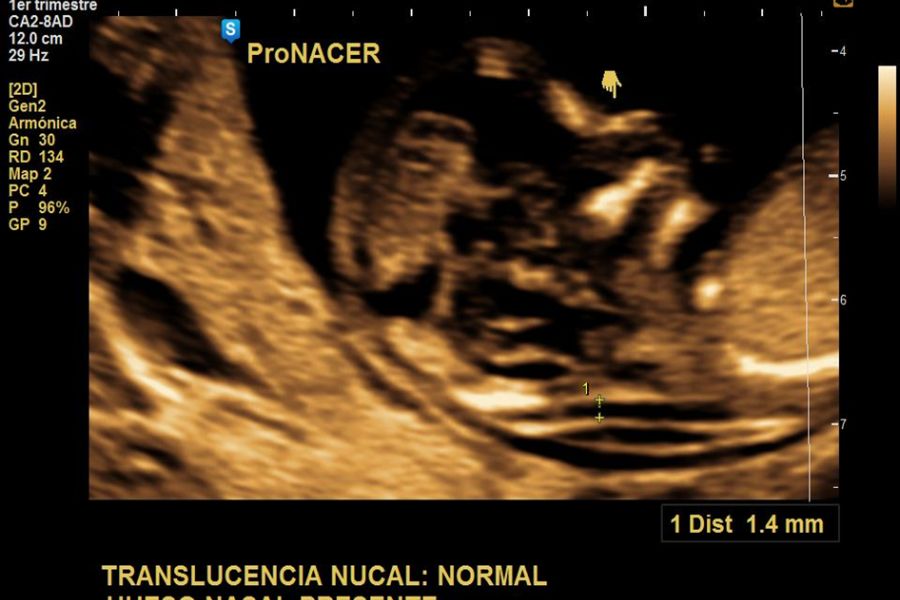

El momento óptimo para realizar el estudio ecográfico para cronicidad y animosidad es el 1er trimestre a partir de la semana 7, 11 a 14 con una sensibilidad > 98%, con una precisión menor pero aceptable en el segundo trimestre temprano (sensibilidad 90%).

Una membrana entre gemelos con el signo “Lambda “indica gemelos dicorionicos. El signo lambda se refiere a la proyección triangular del tejido que se extiende entre las capas de la membrana entremezclada desde una placenta dicorionica fusionada. Se observa mejor a las 10 a 14 semanas, se vuelve menos prominente después de las 20 semanas de gestación y puede desaparecer.